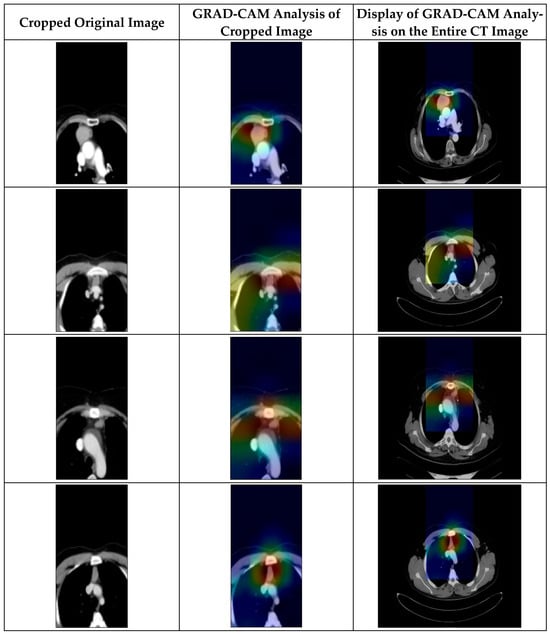

3.6. GRAD-CAM Analysis

Figure 8. GRAD-CAM analysis of CT images of samples with thymoma tumors.